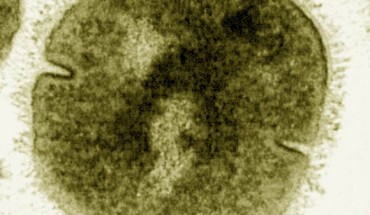

A team of scientists led by Imperial College London has discovered a new subtype of emm89 Streptococcus pyogenes that has contributed to a rise in disease cases in the United Kingdom over the last two decades. Streptococcus pyogenes under the electron microscope (false color). Image credit: Vincent Fischetti, Rockefeller University / CDC. The human pathogen Streptococcus pyogenes (Group A Streptococcus) causes around 600 million infections per year...